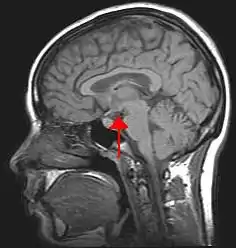

The hypothalamus (from Ancient Greek ὑπό (hupó) 'under', and θάλαμος (thálamos) 'bed') is a part of the brain that contains a number of small nuclei with a variety of functions. One of the most important functions is to link the nervous system to the endocrine system via the pituitary gland. The hypothalamus is located below the thalamus and is part of the limbic system.[1] In the terminology of neuroanatomy, it forms the ventral part of the diencephalon. All vertebrate brains contain a hypothalamus.[2] In humans, it is the size of an almond.

Human brain left dissected midsagittal view

Location of the hypothalamus